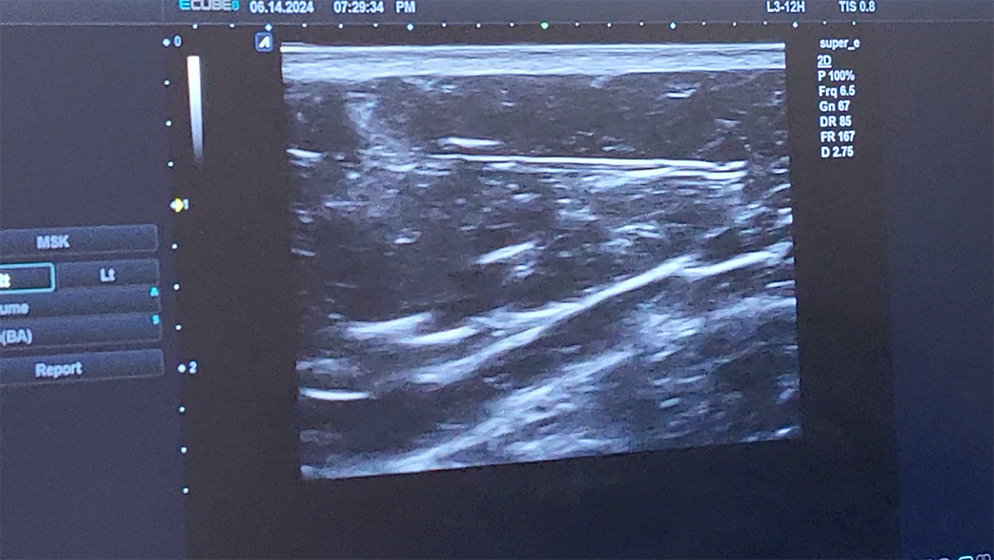

닉스의원에서는 고해상도 초음파를 통해

Scarpa 근막의 실제 깊이를 계측하고

superficial layer와 deep layer를 명확히 구분하며

캐뉼라 팁의 위치를 실시간으로 확인하고

주요 혈관 구조를 시각적으로 확인·회피한 뒤

목표한 층에 약물을 주입합니다.

이 과정은 단순한 ‘안전 보조’가 아니라, 결과의 균일성과 재현성을 확보하기 위한 핵심 절차입니다. 특히 힙딥과 같은 측후면 전환 구간에서는 층 선택의 수 mm 차이가 표면 윤곽의 차이로 이어질 수 있습니다.

해부학적 타겟을 눈으로 확인하고 계측한 뒤 주입하는 것과, 감각에 의존해 깊이를 추정하는 시술 사이에는 결과의 예측 가능성에서 분명한 차이가 존재합니다.